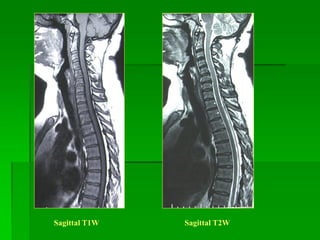

Sagittal T1W Sagittal T2W

 Khởi phát bệnh từ 15-50 tuổi, nữ > nam.

 Vị trí :

- Gđ sớm bệnh ưu thế ở cột sống cổ, gđ sau bệnh phân bố như nhau

ớ các đoạn.

- Thường ở tủy sau bên và không tôn trọng ranh giới xám-trắng.

 MRI: một hay nhiều tổn thương trong tủy giới hạn kém, kéo dài, tín

hiệu thấp trên T1W, cao trên T2W, bắt Gd nếu ở gđ cấp. Tủy phình

hay teo tùy tổn thương cấp hay mạn tính.